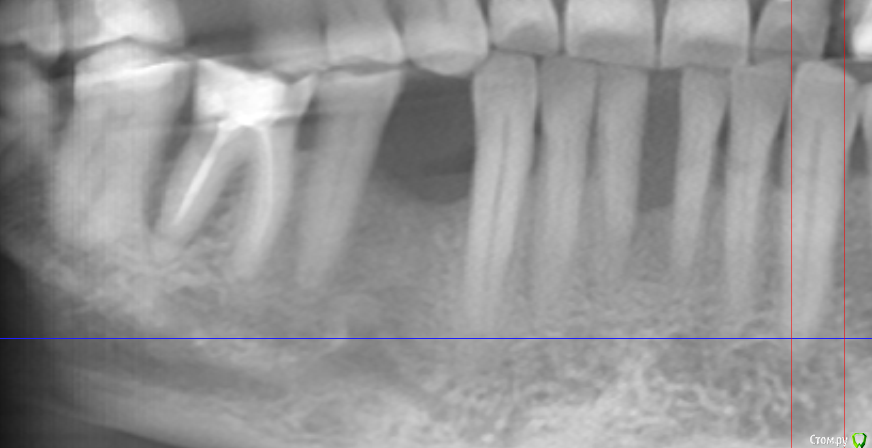

Sergiosse Опубликовано 30 ноября, 2015 Поделиться Опубликовано 30 ноября, 2015 Планируется установка импланта 4,2 х 12мм . Хочется 14 мм ,но боюсь залететь в петлю н\ч канала, т.к.опыт небольшой, а в этой области работаю впервые.На горизонтальном срезе до него всего 2.5 мм. Стоит рисковать ?На практике, что в данном случае дадут лишние 2 мм длинны.? Камрады посоветуйте,с вами мне спокойнее.Да, если торк будет в районе 35-45 Н\см можно сделать временную коронку, или лучше формик поставить?Заранее благодарю за советы. Ссылка на комментарий